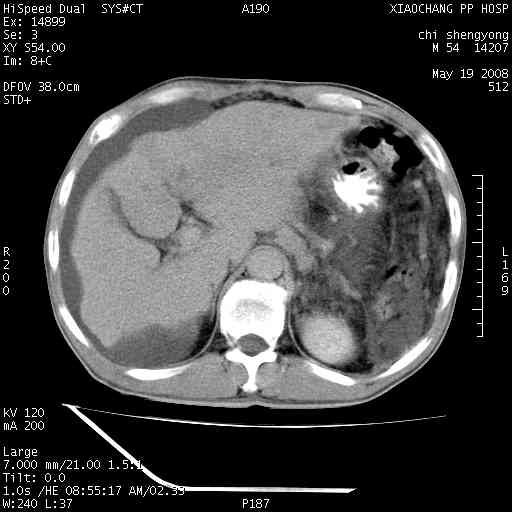

以下是引用zjzjr在2008-5-21 10:52:00的发言:[br]肝左叶巨块型肝癌伴门静脉左支瘤栓形成.肝硬化、腹水,胃底静脉曲张,脾术后改变。

以下是引用随光逐影在2008-5-21 16:20:00的发言:[br]1)肝左叶肝癌伴门静脉左支瘤栓形成,腹膜后淋巴结转移。2)肝硬化、腹水、胃底静脉曲张。3)胆囊炎。4)脾脏缺如,为切除术后所致。